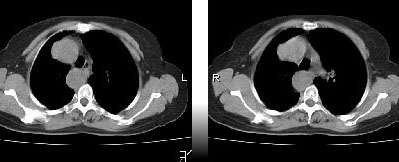

先天发育异常:降主动脉位右侧,主动脉弓形态欠规整。余未见异常影像。

主a弓及降主a都位于右侧,近膈肌时位于椎体前,,左室流出道及其他结构未见明显异常

右位主动脉弓伴迷走左锁骨下动脉。

楼主发布的是右主动脉弓的由中动脉弓并迷走左锁骨下动脉,并不是5楼战友说的全反位。

右位主动脉弓伴迷走左锁骨下动脉